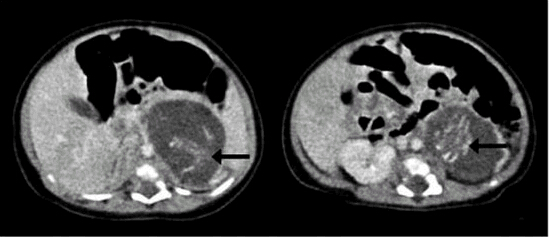

Hong Kong,11/02/2015(El Pueblo en Línea)-El caso de la menor que nació embarazada de gemelos en un hospital de Hong Kong en 2010 no fue más que un caso doble de fetus-in-fetu una enfermedad que se registra en uno de cada medio millón de nacimientos y que no es más que la aparición de fetos no desarrollados en forma de tumor en alguna parte de la anatomía de un recién nacido. En el caso de la menor de Hong Kong, ambos fetos se presentaban en el abdomen.

En un informe presentado por el doctor Yu Kai-man, del hospital Queen Elizabeth de Hong Kong, los especialistas concluyen que las dos masas que presentaba la ni?a en el abdomen eran dos fetos gemelos con un peso de 14,2 gramos y 9,3 gramos respectivamente después de 8 a 10 semanas de gestación. Ambos estaban unidos por el cordón umbilical al abdomen de la menor. Se trata de dos fetos de un embarazo múltiple que no llegaron a desarrollarse y que fueron absorbidos por el feto sano durante su desarrollo en la matriz.

El informe concluye que esta anomalía fue imposible de detectar en el control prenatal dado el reducido tama?o de los fetos.